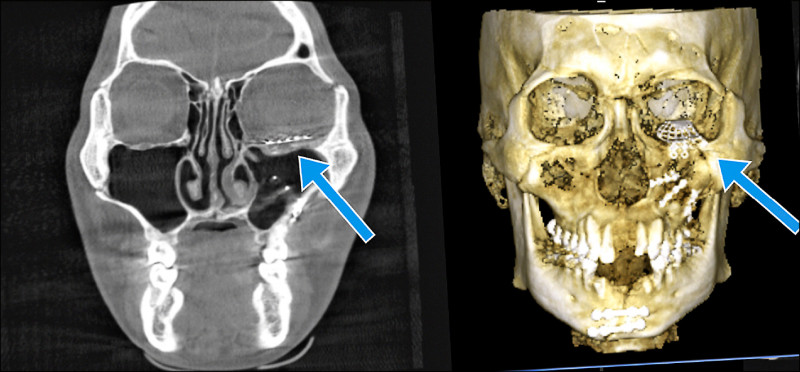

台中榮總口腔顎面外科醫師連凱華指出,陳先生因車禍造成全臉複雜性顏面骨折,上顎、眼底、鼻樑骨、鼻竇、顴骨骨折,下顎、齒槽骨有10多處也骨折缺損,傷勢嚴重,他的眼球下直肌也被骨折碎片夾住,導致眼球下陷,骨折嚴重也造成面部過度腫脹,有致命危機,必須緊急手術。

口腔外科團隊在4小時內利用3D電腦模擬將碎裂的骨頭重新拼好,並製作手術導引板,連凱華從結膜和口內做微創手術,重建破碎的全臉骨骼結構、解除眼球肌肉卡陷、修復薄如紙的眼眶底骨,將顏面各骨塊復位固定,讓陳先生恢復正常咬合與臉型,避免原本瘦長的臉型因骨折而變寬,咬合也恢復密合,成功救命、保眼。

由於陳先生的眼眶骨骨折碎裂嚴重,連凱華再以未骨折的右側眼眶鏡像重建左側,根據3D列印模型預先塑形鈦金屬網板,置入左眼眶重建,進一步解除左眼球肌肉卡陷,重建眼眶底正常結構。